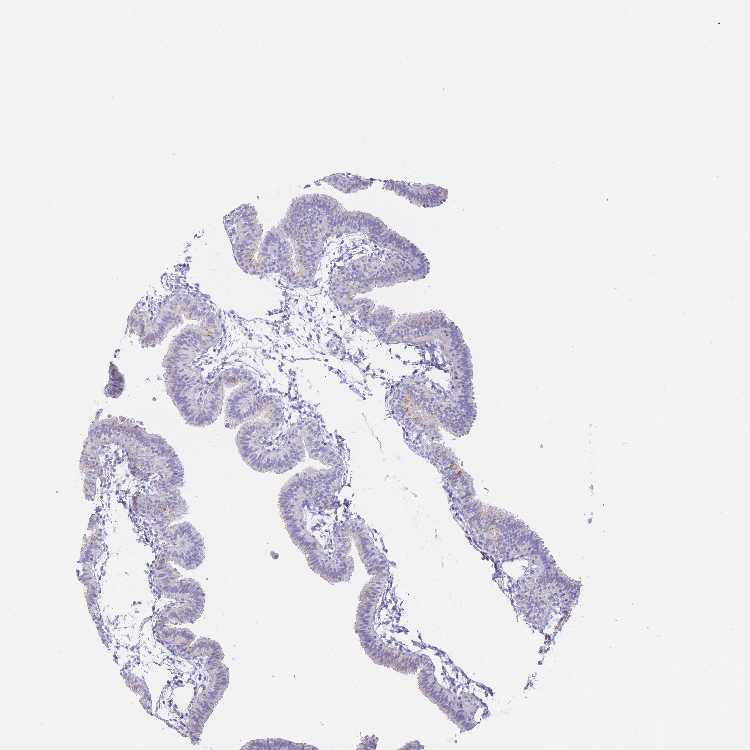

TISSUE PRIMARY DATA FALLOPIAN TUBE Show tissue menu

FALLOPIAN TUBE - Antibody stainingi

Antibody staining in the annotated cell types in the current human tissue is reported as not detected, low, medium, or high, based on conventional immunohistochemistry profiling in selected tissues. This score is based on the combination of the staining intensity and fraction of stained cells.

Each image is clickable and will lead to virtual microscopy that enables deeper exploration of all samples and also displays staining intensity scores, fraction scores and subcellular localization as well as patient and tissue information for each sample.

Antibody HPA026970Antibody HPA029126

Glandular cells LowNot detected